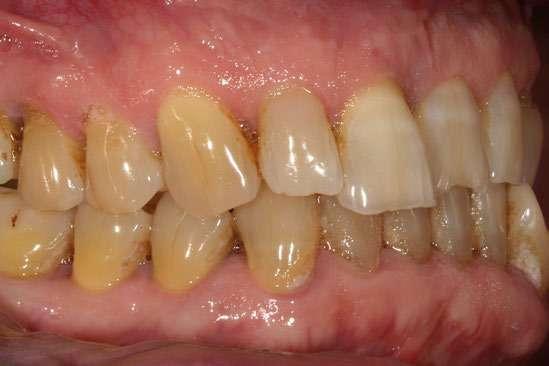

Caso clínico

Presentamos el caso de un paciente masculino de 61 años de edad, bruxista, con evidentes desgastes en toda la dentición y cracks de esmalte que pueden observarse en las fotografías iniciales de la primera visita (figuras 1 y 2). En las fotografías

Figuras 1 y 2. Imágenes intraorales de la primera visita donde se hacen evidentes diferentes desgastes en los dientes anteriores y a mayor detalle crakcs en el esmalte, así como lesiones por abfracción en los cuellos de los dientes de los premolares y caninos superiores.

laterales se ponen de manifiesto aún más varias lesiones de esmalte que indican la parafunción en el paciente, unido a los desgastes excesivos en varias zonas (figuras 3 y 4). El paciente acude por dolor y movilidad en la pieza 11, que se ha incrementado en los últimos días, además de sensación de “diente crecido” que como podemos ver en las fotografías iniciales es real, ya que el diente se encuentra ligeramente extruido en relación con el contralateral. Estos signos parecen indicarnos una fractura o fisura. En la fotografía oclusal, podemos observar el desplazamiento del diente debido a la movilidad (figura 5). Posteriormente se realiza un sondaje positivo de la pieza, que lleva a 11 mm por lo que se confirma la sospecha de fractura y se procede a la exodoncia del diente, realizándose una regeneración posterior del alveolo con PRGF-Endoret y

Figuras 3 y 4. Fotografías laterales donde se evidencian los cracks de esmalte en varios dientes y los desgastes excesivos en varios puntos. En estas imágenes se hacen más evidentes las lesiones por abfracción.

Figura 5. Toma oclusal donde se hace evidente el desplazamiento del diente por el que consulta el paciente, que parece indicarnos una gran pérdida ósea a ese nivel.